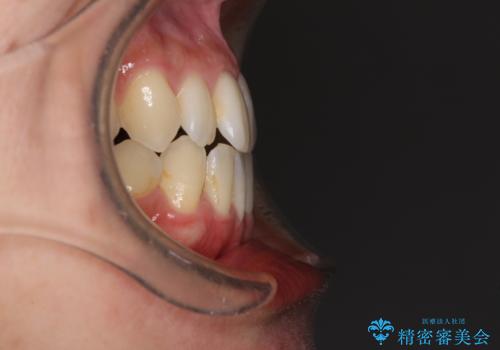

前歯のデコボコ インビザラインによる矯正治療

- 上下前歯の叢生と奥歯の反対咬合を気にして来院された患者様です。

インビザラインを用い、下顎はIPR(歯と歯の間を削る)と歯列全体を後方に移動させ、上顎は側方に拡大させることで歯列を改善していくこととしました。

骨格的に下顎が左側前方にずれているため、上下正中のズレや左右奥歯の咬み合わせを理想的な状態とすることは困難でした。